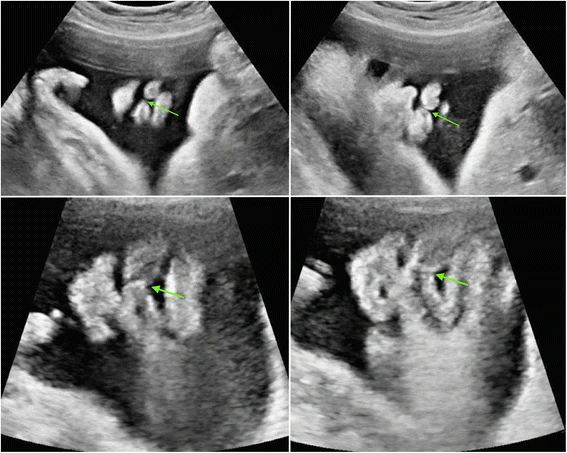

- Yorgun, yaşlı, enfekte, enflamasyonlu, suyu azalmış veya suyu bitmiş, korioamnionitli, miyomlu, polipli, eğri, yarım, bir rahime düşmüş ve yetersizlik – ıstırap çekerek yani survivor içinde (kötü muameleye maruz kalarak) gelişmiş doğmuş, buna katlanmak zorunda kalmış birisi masum doğmaz. Kenz, tekasür, mücadele, rekabet, vurdum duymazlık, savaşma, empatisiz eylemler, fesatlanma, egoizim, cimrilik, hızlıca hasedlenme,… duygularını geliştirerek aslında bunlara yeteneklenerek doğarlar. Ana rahminde temeli atılan bu menfi bilinç düzeyini doğumdan sonra → bu doğal yeteneklerini ilerletirler.

İnsanın ana rahminde, kendisinin de engelleyemediği, katlanmaya maruz kaldığı kötü muameleler onu kötü yapan, kötü yola taşıyan ilk müsebbibtir ve kötülüğe giden yolun taşları ana rahminde atom atom elektron elektron, saniye saniye bilinçlenmektedir. İşte menfi bir rahime maruz kalmanız daha doğmadan bireyin mücadeleci ve saldırgan, kötüye eğilimli bir yapıya bürünmesine neden olabilir.

Anne rahmindeki bu zorluklar, bireyi “masum” olmaktan uzaklaştırır. Bunun yerine, kenz, tekasür, mücadele, rekabet, cimrilik ve haset gibi menfi duygulara yatkın hale getirir.

Bu durum, doğumdan itibaren bireyin doğal bir yetenek gibi bu duyguları geliştirmesiyle devam eder. Kötülüğe giden yolun ilk taşları, ana rahminde döşenir.